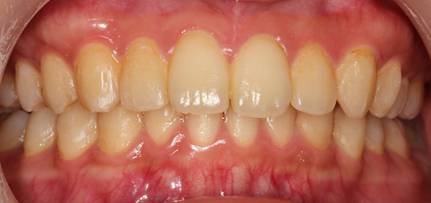

インビザラインによる矯正症例2 22歳女性

治療開始時。正中離開と過蓋咬合がありました

治療途中 5か月後

治療終了 治療開始後7か月